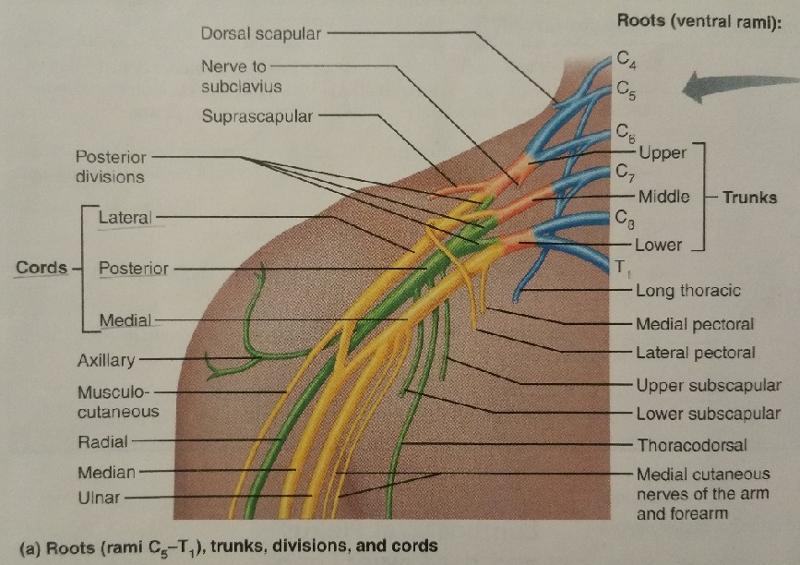

The brachial plexus arises from the ventral rami of what cervical and thoracic nerves?

C5-T1

The brachial plexus after being rearranged consecutively into trunks, divisions, and cords, finally becomes subdivided into what 5 major peripheral nerves?

1. axillary nerve

2. radial nerve

3. median nerve

4. musculocutaneous nerve

5. ulnar nerve

The axillary nerve arises from the ventral rami of what cervical nerves and corresponding cord?

C5-C6 (posterior cord)

The radial nerve arises from the ventral rami of what cervical and thoracic nerves and the corresponding cord?

C5-C8, T1 (medial cord)

The median nerve arises from how many branches, and what are they?

2 branches: medial cord and lateral cord

The respective cords of the median nerve are composed of the ventral rami of which cervical and thoracic nerves?

Medial cord: C8, T1

Lateral cord: C5-C7

The musculocutaneous nerve arises from the ventral rami of which cervical nerves and its corresponding cord?

C5-C7 (lateral cord)

The ulnar nerve arises from the ventral rami of which cervical and thoracic nerves and the corresponding cord?

C8, T1 (medial cord)

Identify the blanks.